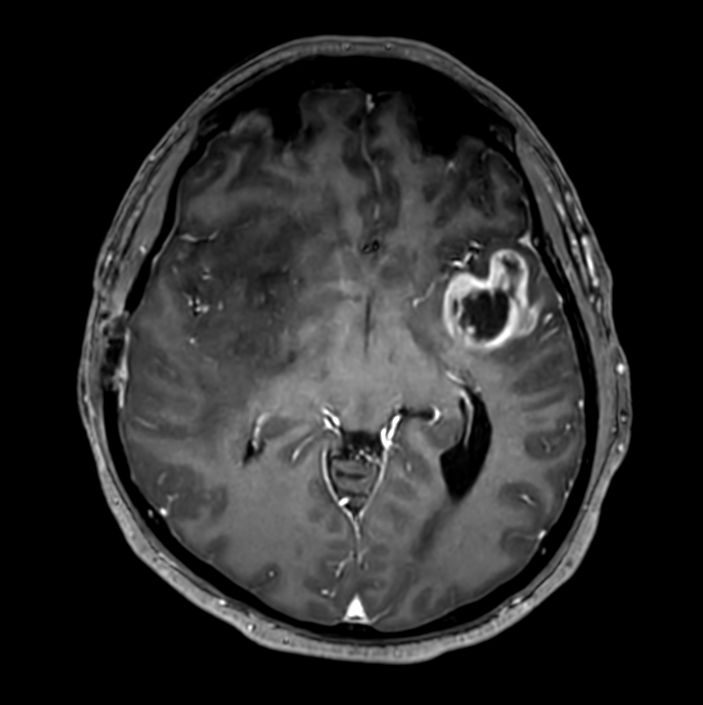

Large lesion brain imaging with synthetic MRI

Patient with a large brain lesion. AI based SmartSpeed is utlized to shorten scan time without compromise in image quality. Advanced imaging techniques like pCASL and 3D APT are used to perform contrast-free brain imaging to assess perfusion and tumoral activity. SWIp 3D susceptibility weighted offers the high sensitivity required to visualize deoxygenated (venous) blood or calcium deposits. A single synthetic (SyntAc) brain quantification scan is added. The resulting data of this scan can be used as input for advanced third party processing software* to synthesize MR images with different contrasts, brain parenchyma fraction maps and/or brain segmentation maps.

Sagittal 3D T1w TFEPost-Gado

3D T1w TFE (Axial reformat)Post-Gado